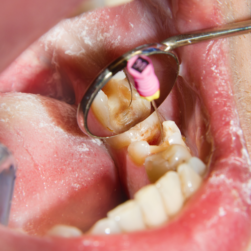

Digital root canal treatment uses advanced dental technology to accurately remove infection while preserving natural tooth structure and function.

It works through digital imaging and guided instruments to clean, disinfect, and seal root canals precisely.

Digital tools allow precise diagnosis and targeted treatment while protecting healthy surrounding tooth structure.